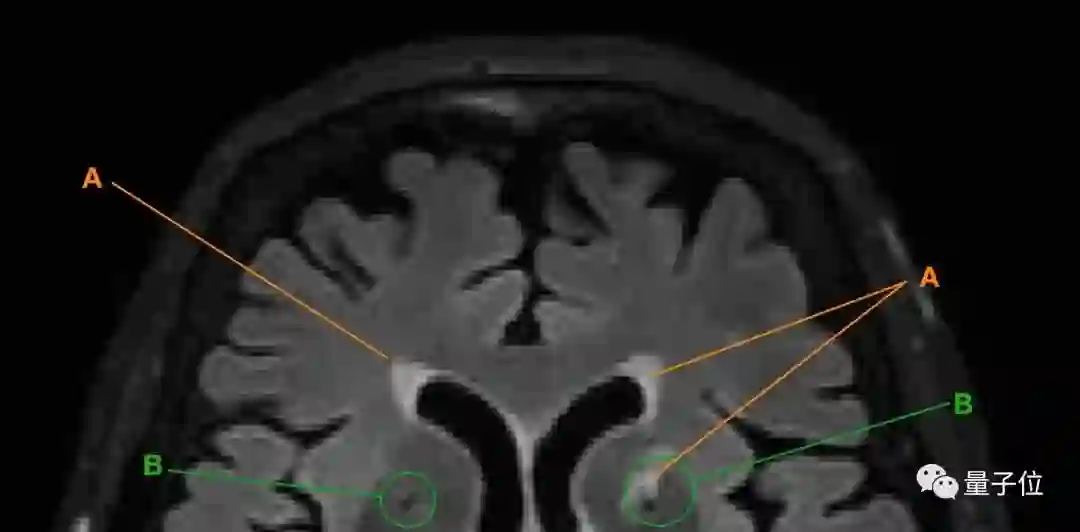

得出以上结论,研究人员主要是通过追踪老人大脑中脑白质高信号(WMH)腔隙的变化来实现的。

A为脑白质高信号;B为腔隙

以上两种现象都是脑小血管病(CSVD)的主要表现。